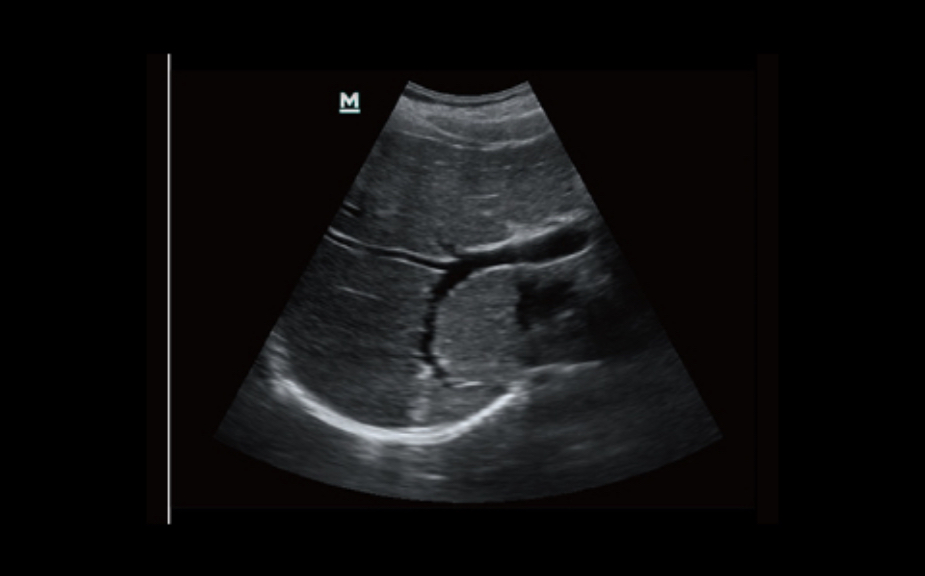

PSH TM (Phase-shifted imaging of harmonics)

Pure harmonic imaging for better contrast resolution providing sharper images with excellent resolution and less noise.

Ipimtm

It allows using multiple scanned angles to compose one image, which improves contrast resolution and improves visualization.

ECLORTM

Get improved image quality based on automatic structure detection

- Sharper and more continuous edges

- Smooth and uniform tissue

- Cleaner areas “without Echo”

ESKIPTM

Get a complete and extended view of the anatomical structure with panoramic imaging along with the speed indicator and the ability to scan forward / backward making scanning easier, smoother and more controllable.

External field of view

Discover better diagnostic information with an expanded view of the anatomical structure on all convex and linear probes.

B-STERTM

Your tool for a deeper biopsy: allows adjustments to the scan line for a better view of the needle, nerves and small vessels